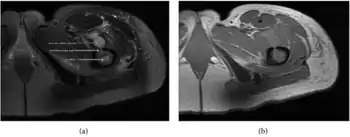

| a,b) MRI showing the Brodie's abscess in the left proximal femur | |